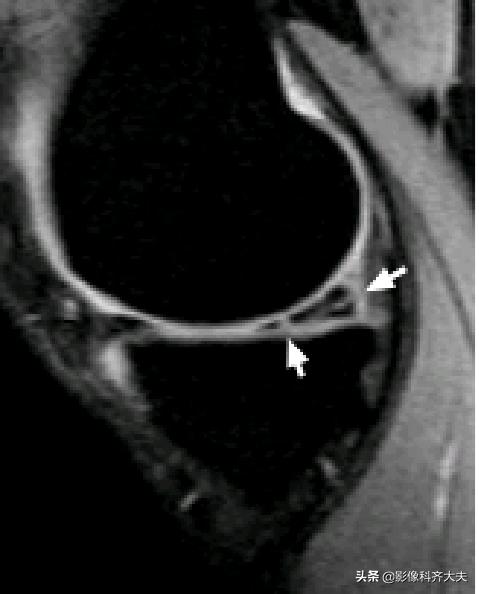

膝横韧带:

腘肌腱腱鞘:

后股板韧带:

关节内气体伪影:

内侧半月板后角上隐窝: